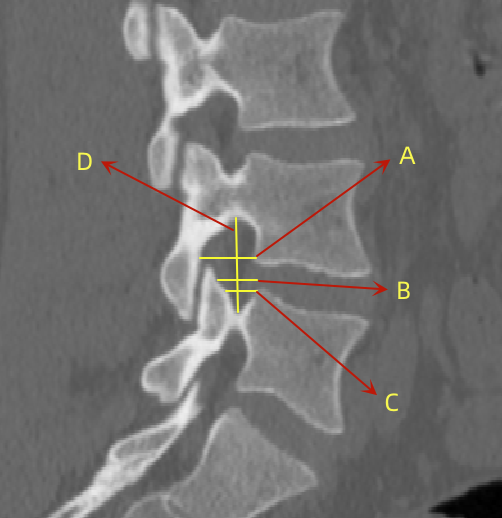

2、通过术前CT测量L4-5节段手术部位的(1)上位椎体后下角水平方向到关节突关节的距离(A);(2)纤维环后缘的中点水平方向到关节突关节的距离(B);(3)下位椎体后上角水平到关节突的距离(C);(4)上位椎体的椎弓下切迹与下位椎体椎弓上切迹连线的距离(D),图 6;(5)在手术节段的棘突矢状位CT层测量椎间隙高度(E),图 7;(6)在手术节段的关节突关节横截面CT层测量关节突间距离(F),图 8,再通过术中及术后CT判断患者椎间孔成型级别,将A-F测量数据与5级成型中的各级别成型进行相关性分析。

图 6 A-D的测量方式 |